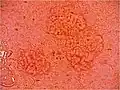

Sebaceous hyperplasia shares histopathological similarities with the typical architecture of the folliculosebaceous unit, but with larger and expanded sebaceous glands.[12][13]

H&E staining of biopsied lesion of sebaceous hyperplasia: Note the multiple, mature sebaceous lobules attached to the central dilated duct in the upper dermis. -